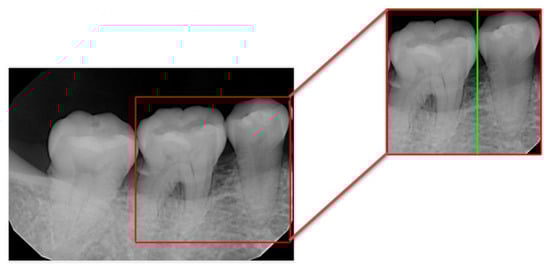

2.2. Image Segmentation

2.2.1. Vertical Projection